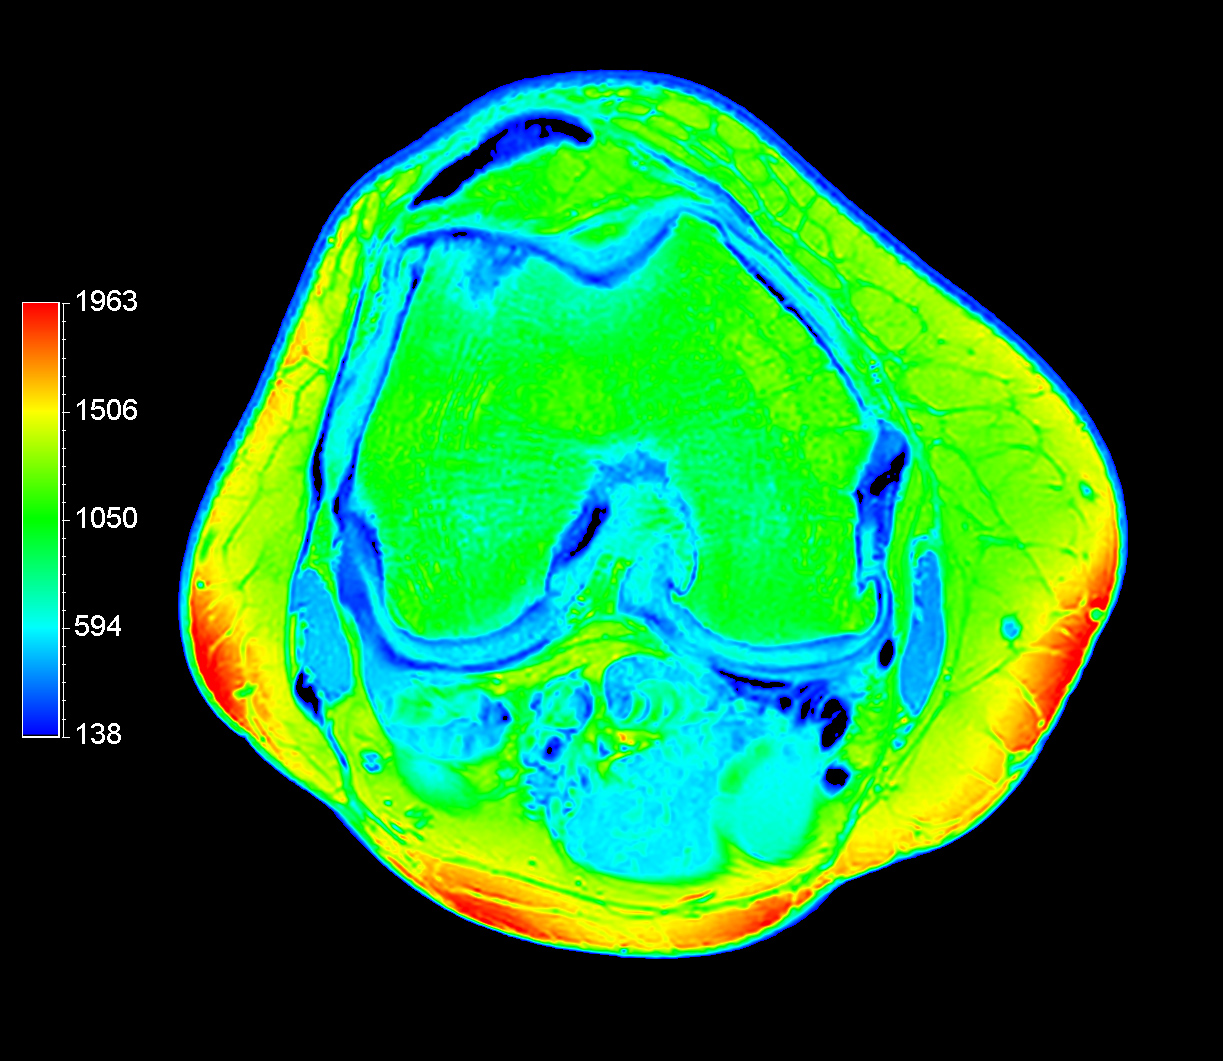

Axial T2w calc